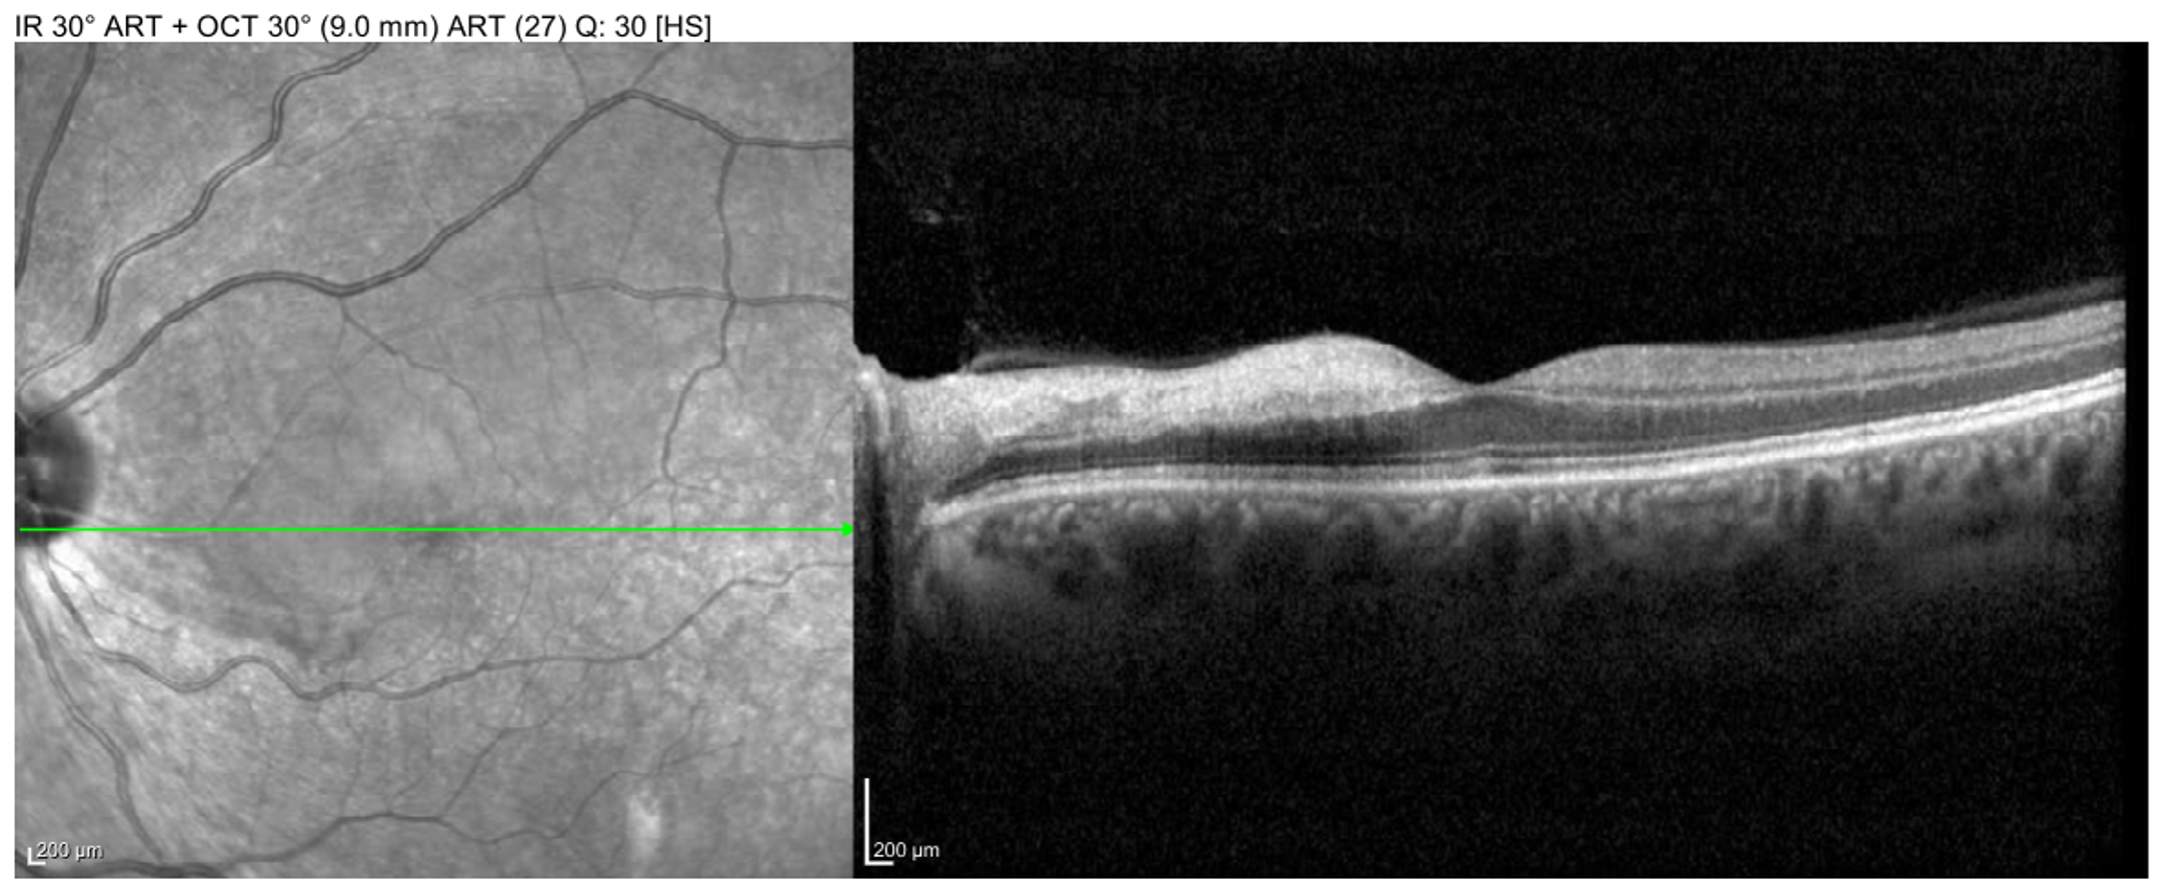

• OCT Macula (Figures 5 and 6):

• OD: one superior area of BRAO visible on near infrared

• OS: large superior BRAO involving the macula

Macula OCT of the right eye showing a small superior BRAO visible on near-infrared en-face image.

Enlarge Download

Figure 5. Macula OCT of the right eye showing a small superior BRAO visible on near-infrared en-face image.

Macula OCT of the left eye showing large BRAO in the macula with inner-retinal edema and hyperreflectivity.

Figure 6. Macula OCT of the left eye showing large BRAO in the macula with inner-retinal edema and hyperreflectivity.